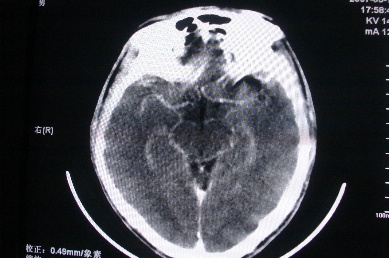

以下是引用zhangzhongshou在2007-4-18 17:49:00的发言:[br]脑实质内多发高密度结节影,支持肉芽肿得诊断,究竟是结核性、真菌性或寄生虫性的需结合临床,进一步检查确诊,但从影像上无法鉴别,只是临床上结核性肉芽肿最为多见而已。